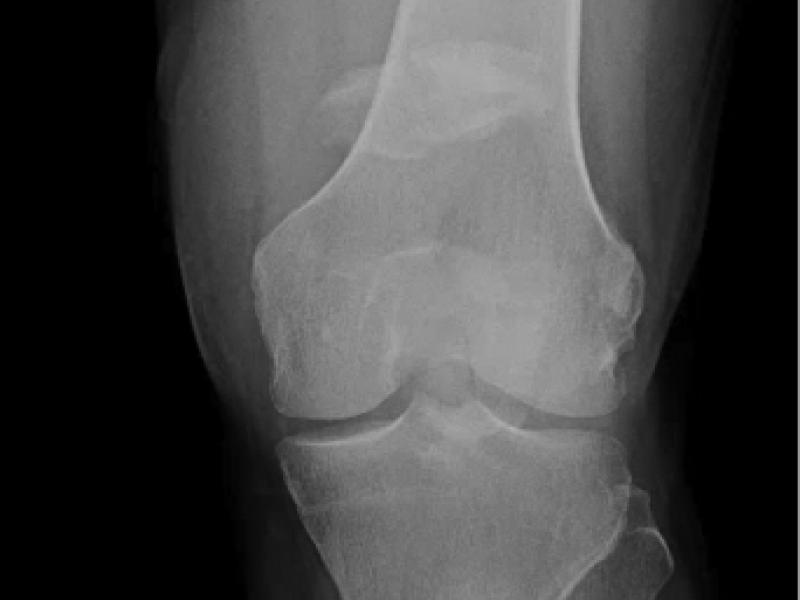

A 59 yo male presented to the Emergency Department after a